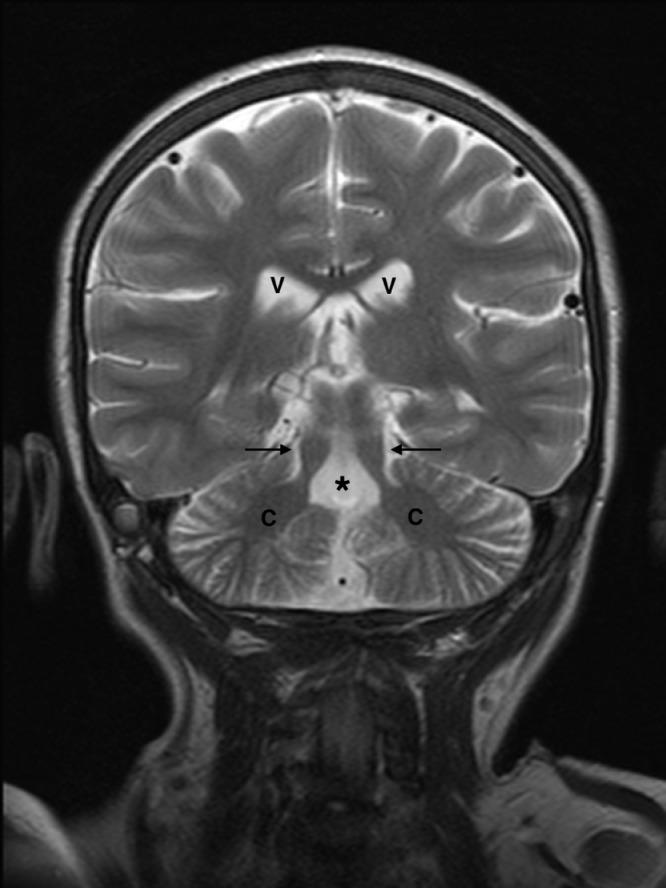

Joubert Syndrome, manifests in a spectrum of neurological symptoms. This case describes a 7-year-old girl with perinatal complications, and subsequent neurodevelopmental challenges. An MRI confirmed the diagnosis of Joubert syndrome, with the distinctive "molar tooth sign" being a key imaging characteristic. Approximately 25% of cases exhibit nephronophthisis, impacting kidney function, further complicating the clinical picture. Diagnosis relies on imaging and management necessitates a multidisciplinary approach, addressing symptoms and complications, with prognosis linked to the presence of organic disease. The case emphasizes the significance of a multidisciplinary strategy, including genetic counseling, and underscores the diverse manifestations of this syndrome. Prenatal identification through ultrasound and MRI plays a crucial role in diagnosing and treating this rare condition.

乔伯特综合征表现为一系列神经症状。本病例描述了一名7岁女孩,有围产期并发症及随后的神经发育挑战。磁共振成像(MRI)确诊为乔伯特综合征,其独特的“磨牙征”是关键的影像学特征。约25%的病例出现肾单位肾痨,影响肾功能,使临床情况更加复杂。诊断依靠影像学检查,治疗需要多学科方法,处理症状和并发症,预后与器质性疾病的存在有关。该病例强调了包括遗传咨询在内的多学科策略的重要性,并突出了该综合征的多样表现。通过超声和MRI进行产前识别在诊断和治疗这种罕见疾病中起着关键作用。